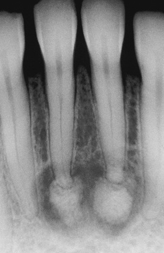

periapical cemento-osseous dysplasia